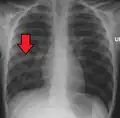

| Chest X-ray of a pneumonia caused by influenza and Haemophilus influenzae, with patchy consolidations, mainly in the right upper lobe (arrow) | |

X-ray presentations of pneumonia may be classified as lobar pneumonia, bronchopneumonia, lobular pneumonia, and interstitial pneumonia.[75] Bacterial, community-acquired pneumonia classically show lung consolidation of one lung segmental lobe, which is known as lobar pneumonia.[42] However, findings may vary, and other patterns are common in other types of pneumonia.[42] Aspiration pneumonia may present with bilateral opacities primarily in the bases of the lungs and on the right side.[42] Radiographs of viral pneumonia may appear normal, appear hyper-inflated, have bilateral patchy areas, or present similar to bacterial pneumonia with lobar consolidation.[42] Radiologic findings may not be present in the early stages of the disease, especially in the presence of dehydration, or may be difficult to interpret in the obese or those with a history of lung disease.[24] Complications such as pleural effusion may also be found on chest radiographs. Laterolateral chest radiographs can increase the diagnostic accuracy of lung consolidation and pleural effusion.[41]

Right middle lobe pneumonia in a child as seen on plain X-ray

Right middle lobe pneumonia in a child as seen on plain X-ray